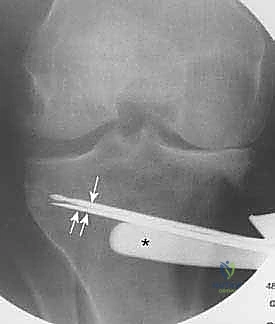

يتم عمل شق جراحي دقيق في الجزء الداخلي العلوي من عظمة الساق (الظنبوب)، مع الحرص الشديد على حماية الأعصاب والأوعية الدموية المحيطة بالركبة.

3. إجراء القطع العظمي (The Osteotomy):

باستخدام أدوات دقيقة ومناشير جراحية متطورة، يتم عمل قطع غير مكتمل في عظمة الساق. هناك طريقتان رئيسيتان:

* الشق المفتوح (Opening Wedge): يتم فتح العظم من الداخل وإضافة طعم عظمي (صناعي أو طبيعي) لملء الفراغ وتعديل الزاوية. وهي الطريقة الأكثر شيوعاً حالياً.